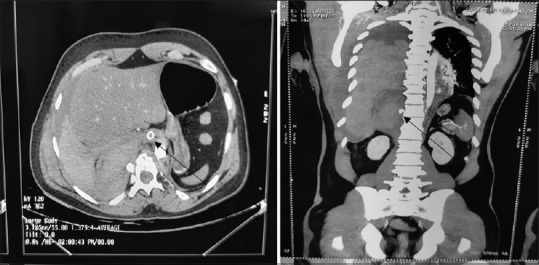

肋间动脉瘤是一种血管异常,具有潜在的破裂风险,可能导致危及生命的血胸。本病例报告介绍一位年轻男性,他经历了肋间动脉瘤破裂,随后在剧烈运动后出现大量血胸。目前的病例研究揭示了在周边环境下处理此类病例的困难和经验教训,包括是否插入肋间胸引流管(ICD)的困境。患者最终被诊断为一种罕见的临床症状,即右侧后肋间动脉瘤破裂伴大量血胸。

Abstract: Intercostal artery aneurysms are a type of vascular abnormality that poses a potential risk of rupture, which could lead to life-threatening hemothorax. This case report presents a young male who experienced a rupture of an intercostal artery aneurysm and subsequently suffered from a massive hemothorax after engaging in strenuous physical activity. The current case study sheds light on the difficulties and lessons learned in managing such cases in peripheral settings, including the dilemma of whether to insert an intercostal chest drain (ICD). The patient was ultimately diagnosed with a rare clinical entity known as rupture of right posterior intercostal artery aneurysm with massive hemothorax.